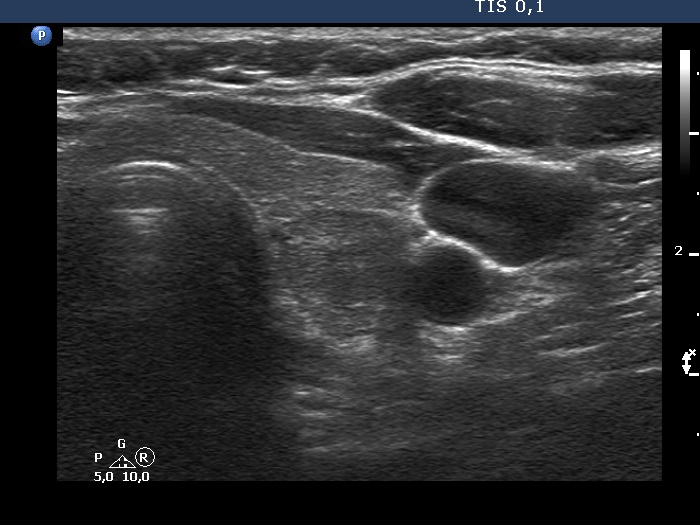

Ultrasonography. The thyroid was echonormal. According to the PET-positive lesion, there was a moderately hypoechoic nodule in the middle-dorsal part of the left lobe. The lesion presented with perinodular blood flow. In the transverse section, it appeared that there was another nodule in the lower pole of the lobe. At the same time, based on the longitudinal section, it was not an oval, nodule-like lesion. The mass proved to be longitudinally elongated in the caudal direction and was avascular.